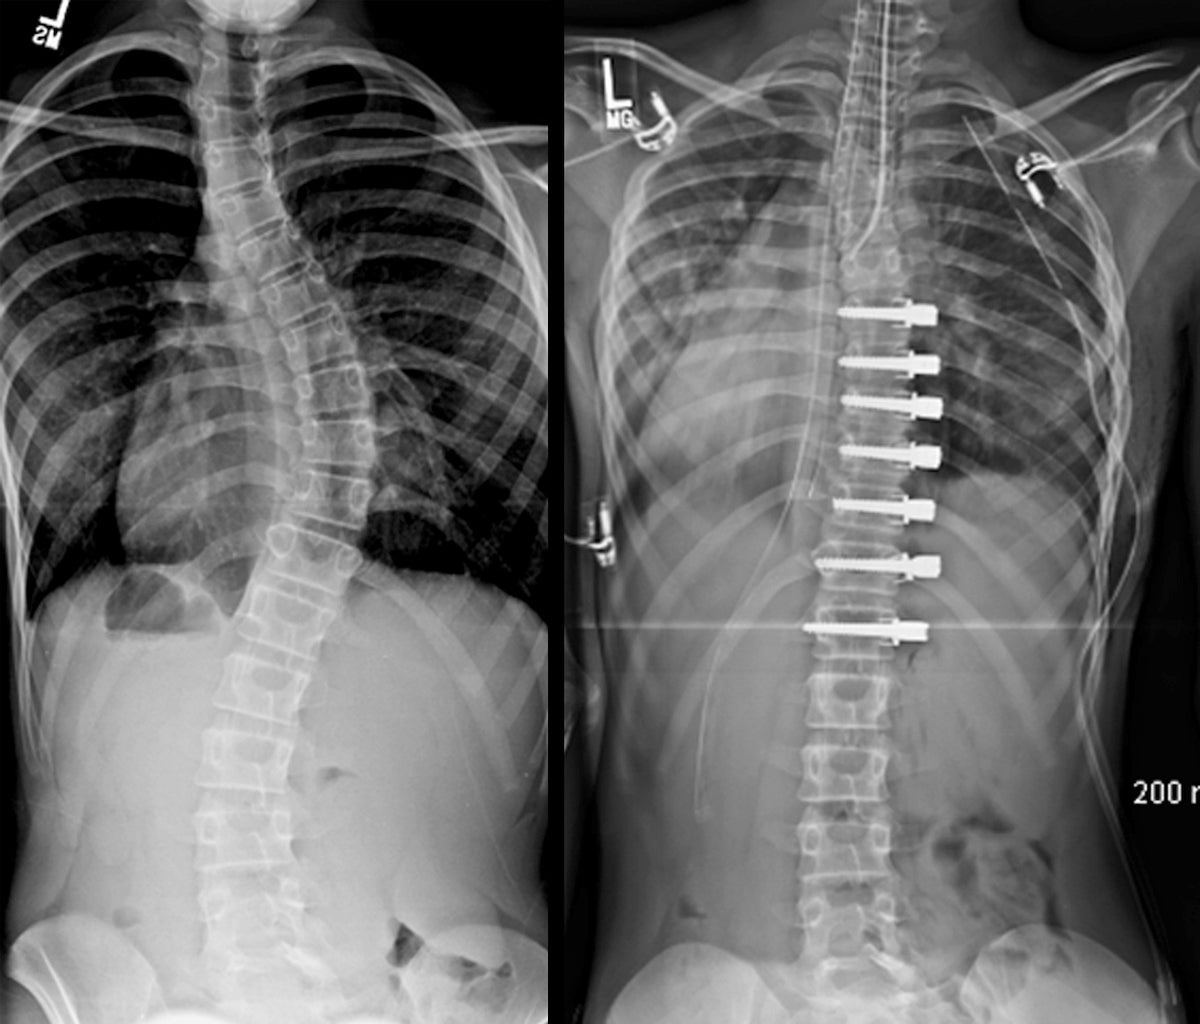

Измерение кифоза грудного отдела: Рентгеновские снимки